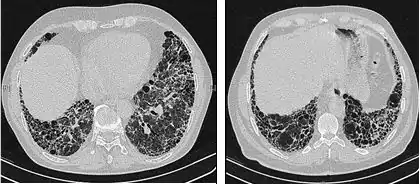

L’évaluation radiologique par tomodensitométrie haute résolution est capitale dans le diagnostic de la fibrose pulmonaire idiopathique. La tomographie axiale calculée par ordinateur est réalisée à l’aide d’un scanner, sans injection d’agents de contraste. Les coupes sont très fines (1–2 mm).

La tomodensitométrie haute résolution typique en cas de fibrose pulmonaire idiopathique fait apparaître des altérations fibrotiques des deux poumons, en particulier à la base et en périphérie. Selon les recommandations conjointes de l’ATS, l’ERS, la JRS et l’ALAT de 2001, la tomodensitométrie haute résolution est une composante essentielle du diagnostic de fibrose pulmonaire idiopathique, qui permet d’identifier la pneumopathie interstitielle usuelle grâce à la présence de signes suivants à répartition typiquement basale et périphérique bien que souvent inégale[1]:

- opacités réticulaires, souvent associées à une bronchiectasie par traction ;

- réticulations intralobulaires, plus étendues que les plages de verre dépolies (ces dernières sont rares dans la FPI)

- images en rayons de miel se manifestant sous forme de cavités kystiques, en général de diamètres comparables (3–10 mm) mais souvent assez grandes, sous-pleurales et caractérisées par des parois bien définies et disposées en au moins deux rangées (La présence d’une seule rangée de kystes ne suffit pas à évoquer des nids d’abeille) ;

- la répartition est typiquement basale et périphérique bien que souvent inégale.